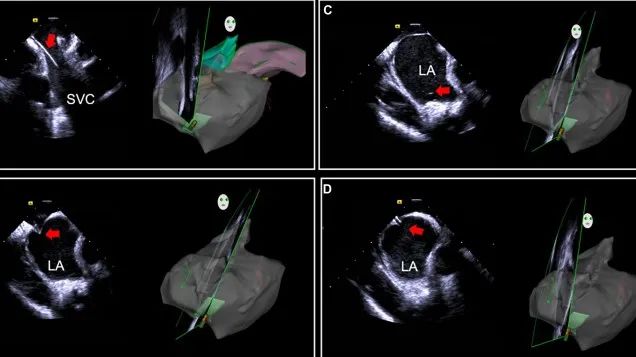

一種與心導(dǎo)管檢查相結(jié)合的超聲心動圖診斷新興技術(shù),通過將超聲探頭置于心腔內(nèi)部,發(fā)射并接收超聲信號,來精確獲取心臟解剖結(jié)構(gòu)、心臟血流動力學(xué)等信息的實時成像。與其他影像技術(shù)相比,ICE技術(shù)具有操作簡單、無輻射、安全性高、手術(shù)效率高、實用等優(yōu)勢,ICE在很大程度上有望取代經(jīng)食道超聲心動圖(TEE),成為電生理和結(jié)構(gòu)性心臟病領(lǐng)域的理想成像方式。

目前ICE技術(shù)已被應(yīng)用于左心耳封堵、房顫射頻消融、二尖瓣成形、房間隔缺損封堵等多種心臟介入手術(shù),應(yīng)用場景主要圍繞心臟電生理、結(jié)構(gòu)性心臟病等領(lǐng)域,目前以電生理應(yīng)用為主。數(shù)據(jù)顯示,我國結(jié)構(gòu)性心臟病介入器械市場規(guī)模已從2017年的4億元增長至2021年的20億元,年復(fù)合增長率達(dá)48.3%;預(yù)計到2025年,該市場規(guī)模將達(dá)到104億元,可以預(yù)見ICE市場規(guī)模也將同步高速增長,未來市場發(fā)展空間廣闊。

心腔內(nèi)超聲(ICE)技術(shù)壁壘極高,國內(nèi)主要廠商核心部件仍舊為進(jìn)口,集成了超聲和圖像處理最前端技術(shù),包括超聲探頭、線纜、軟件成像算法等,是當(dāng)前內(nèi)窺超聲方向最具挑戰(zhàn)的領(lǐng)域。ICE的應(yīng)用經(jīng)歷了2D平面成像、3D三維立體成像、以及4D的實時三維立體成像階段。